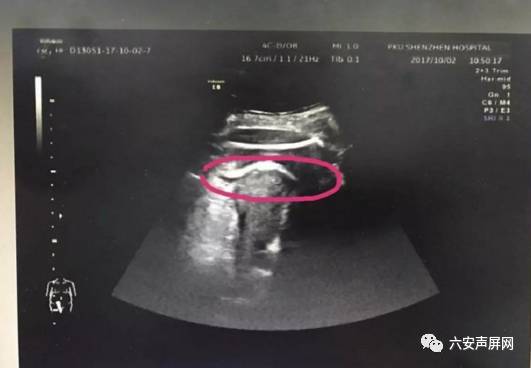

医生初步怀疑患者子宫破裂,当即安排做了B超。检查发现,胎儿的一条腿“踢破”了子宫,进入了腹腔,大腿根正卡在子宫壁上!

▲红色圆圈处是胎儿的腿,已经伸到子宫壁外

医生追问患者病史,原来张女士2016年做过子宫肌瘤剔除术,术后半年就怀孕了。不到2分钟B超检查,仅凭有限病史,医生快速作出诊断:高度怀疑为疤痕子宫破裂。